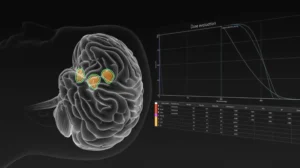

La intersecția dintre tehnologie și îngrijire medicală, ICCO EMS oferă echipamente și servicii inovatoare pentru neurochirurgie, radioterapie, radioprotecție, iradiere sânge și recuperare medicală.

Furnizăm echipamente medicale avansate, selectate pentru performanță, siguranță și fiabilitate în domenii critice precum oncologia, radioterapia și neurochirurgia.

Verificare echipamente de radioprotecție

Siguranța utilizatorilor este prioritară. Evaluăm periodic eficiența echipamentelor radioprotectoare pentru a asigura protecție maximă împotriva radiațiilor ionizante.